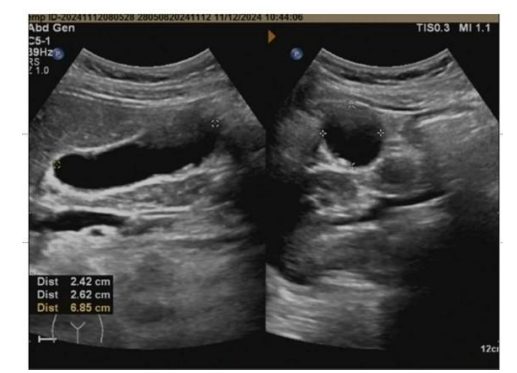

Undescended Testes: The Hidden Normal or Abnormal Anatomy and The Value of Laparoscopy